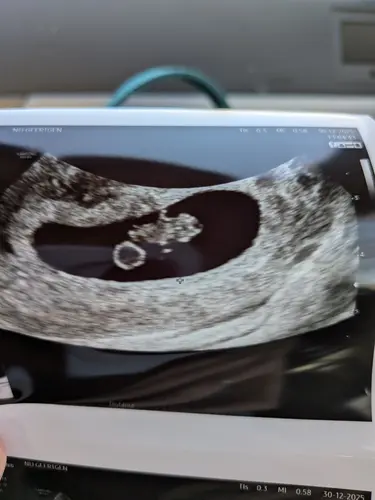

Vandaag een herhaal vitaliteitsecho gehad. Omdat ik 2 weken terug al 7+2 weken dacht te zijn bij de eerste vitaliteitsecho, maar werd teruggezet naar 6+2 weken. Voor mijn eigen gemoedsrust kreeg ik vandaag nog een herhaling. Nu bleek ik toch bijna 9 weken te zijn. Super blij en opgelucht. 🫶🏼🩵🩷